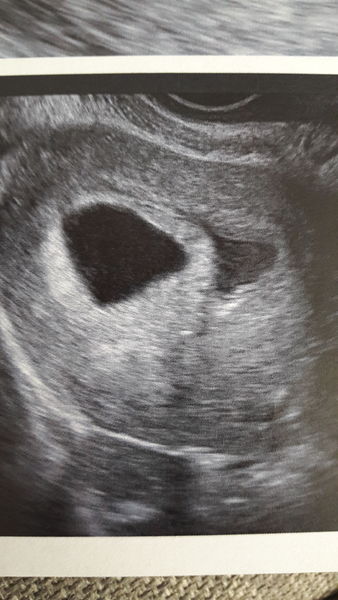

Baby is there, with a heartbeat and matching my dates exactly of 6w2d giving me EDD of 26/4/18

I don't feel out of the woods just yet but I am certainly very very relieved. My little rainbow baby Smile

Anyone got any experience of subchorionic haematoma? The sonographer took quite a lot of pics and told me I have a blood clot and showed me and said to mention to mw tomorrow.

The sack is on the left and the bleed is on the right... anyone? !

Babies due in April 2018